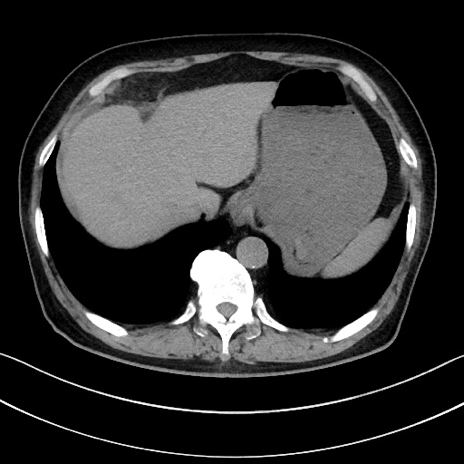

冠状断像

【症例】70歳代男性

【主訴】腹痛

【現病歴】今朝から腹痛あり。全体的に痛い。特に左上の方。排ガスが今日はない。冷や汗が出る。

【既往歴】直腸癌術後

【身体所見】左側腹部〜上腹部に圧痛あり。腹膜刺激症状明らかなではない。軽度反跳痛。左下腹部に術後瘢痕あり。

【データ】WBC 7700、CRP 0.02